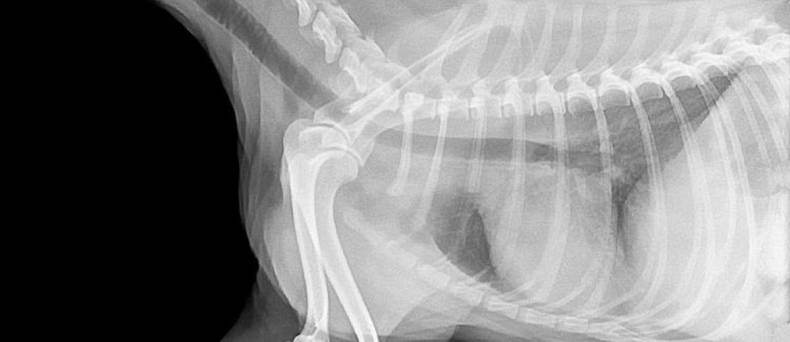

Een radiografie neemt een opname van de doorgelaten straling door het lichaam van de patiënt. Deze straling wordt door verschillende weefsels op een verschillende manier tegengehouden. Vooral dichte structuren zoals beenderen houden relatief veel straling tegen. Bij een contrast radiografie spuit men bepaalde stoffen in waarvan men weet dat ze veel straling tegenhouden, zoals barium.

Dit kan erg nuttig zijn om structuren die anders niet goed zichtbaar zijn, beter te kunnen zien op de radiografie. In sommige gevallen zal men lucht inspuiten om weinig straling tegen te houden. Dit kan ook gecombineerd worden met 'donker' contrast.